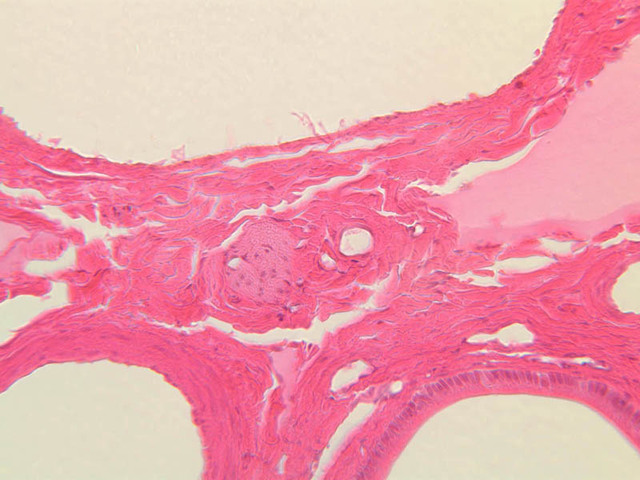

Now turn your attention to the system of pancreatic ducts. As you look for duct elements, bear in mind that the nuclei of duct cells tend to stain more lightly and to have less prominent nucleoli than do those of acinar cells. Begin by studying a number of different acini until you have identified several examples of centroacinar cells, which represent the initial segment of the duct system. Centroacinar cells are usually evident as lightly stained nuclei that lie, individually or in clusters of two or three, near the center of an acinus. Now look along the boundaries between acini for intercalated ducts (B-36, H&E [10x, 20x, 40x-labeled] [10x, 20x, 40x]), which appear in longitudinal section as trains of elongate, lightly stained nuclei and in transverse section as closely spaced, lightly stained nuclei surrounding a small lumen. Intercalated ducts drain into intralobular ducts, which are distinguished by their larger diameter. It is best to use the 10X objective as you begin your search for intralobular ducts (B-36, H&E [10x, 20x, 40x-labeled] [10x, 20x, 40x]). You want to be on the lookout for arrays of closely spaced nuclei surrounding a lumen. Conclude your study of the duct system by examining the connective tissue between pancreatic lobules for interlobular ducts, which may vary in caliber and epithelial lining (B-36, H&E [10x-labeled, 20x, 40x]).

6 Intralobular Duct InD H&E b36 interlobular duct pancreas 10x labeled.jpgB36, Pancreas, 10x; b36 intralobular collecting duct pancreas 40x labeled.jpgB36, Pancreas, 40x

7 Interlobular Duct IrD H&E b36 interlobular duct pancreas 10x labeled.jpgB36, Pancreas, 10x

8 Connective Tissue CT H&E b36 interlobular duct pancreas 10x labeled.jpgB36, Pancreas, 10x